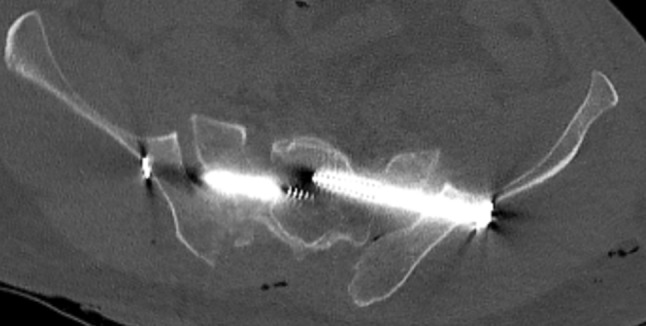

Fig. 3.

Anterior sacral dislocation and insertion of bilateral SI-screws causing nerve palsies

The eight patients with mal-placed implants consisted of three patients with SI-screws, of which 1 SI-screw penetrated to the ipsilateral S1 root, 1 SI-screw penetrated the contralateral sacral wall inducing L5-root symptom and the third case was bilateral SI-screws causing anterior displacement of the sacral body causing L5-S1 symptoms (Figs. 1, 2, 3). In addition, there were three cases of screw penetration to the hip joint following anterior column fixation of acetabular fractures, whereof 2 were found early on the post-operative CT scans, and 1 was found during THR surgery 2.5 years later. Finally, there was 1 case with 2 SI-screws who needed screw tightening. The last case of mal-placed implant was an anterior SI-joint plate placed too medial and thereby causing local L5-root symptom. Implant failure occurred in six cases: 3 posterior wall acetabular fractures with loss of reduction, 2 anterior symphyseal plates with loss of reduction and 1 plated trans iliac wing fracture with loss of reduction. Details on patients reoperated due to hardware-related problems are given in Table 5. The median (IQR) hospital length of stay was 23 (10–44) days for patients who underwent a reoperation during their primary hospital stay, compared to 18 (10–25) for surgically treated patients who were not reoperated (p = 0.2).